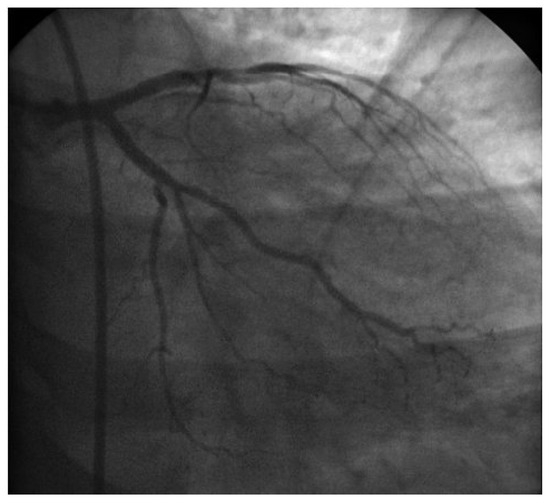

Der 70-jährige Patient wurde uns zugewiesen zur stationären kardialen Rehabilitation bei St. n. mechanischem Aortenklappenersatz wegen schwerer degenerativer Aortenstenose.[...]